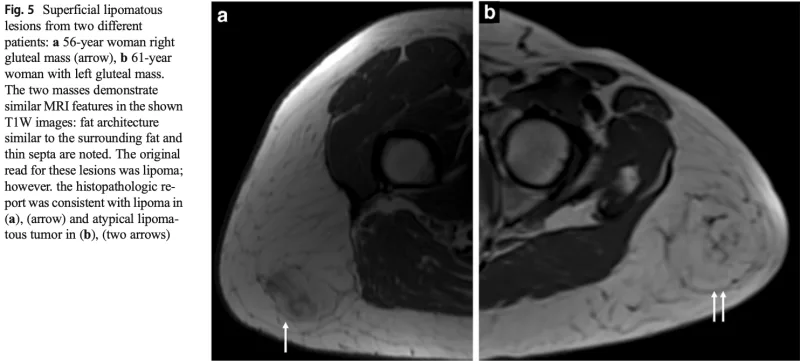

aは良性の脂肪腫, bは良悪性中間型の異型脂肪腫様腫瘍.

どちらも皮下脂肪との境界が不明瞭です.

MRIを撮像した結果, 皮下脂肪の肥厚を認めるものの, 腫瘍の再発かどうかは判断できませんでした.